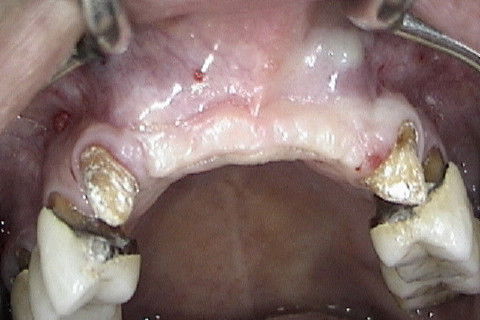

Vista oclusal da região anterior da maxila, antes da reabertura

Incisões horizontais e verticais para expor os implantes

Rebatimento do retalho e exposição dos implantes